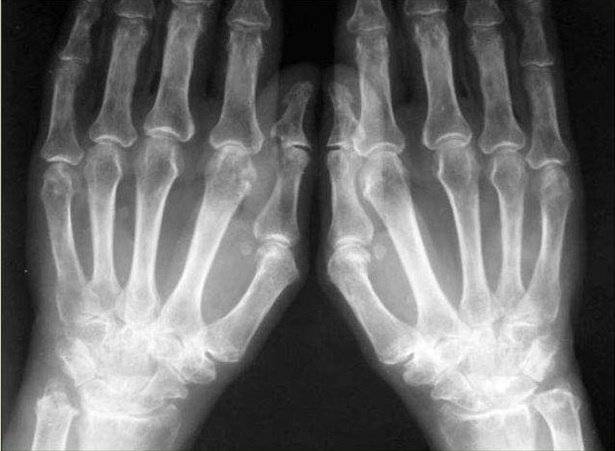

Рентгенологические признаки артрита на разных стадиях

Первыми страдают мелкие суставы кистей рук, стоп. Рентгенологические признаки первой стадии ревматоидного артрита:

- преимущественное воспаление мягкотканого компонента, имеющее вид уплотнений структур над поражённым суставом;

- незначительное сужение межсуставной щели, которое не визуализируется на рентгеновском снимке;

- начальные проявления остеопороза в виде локальных просветлений костных структур и разрыхления только суставных поверхностей.